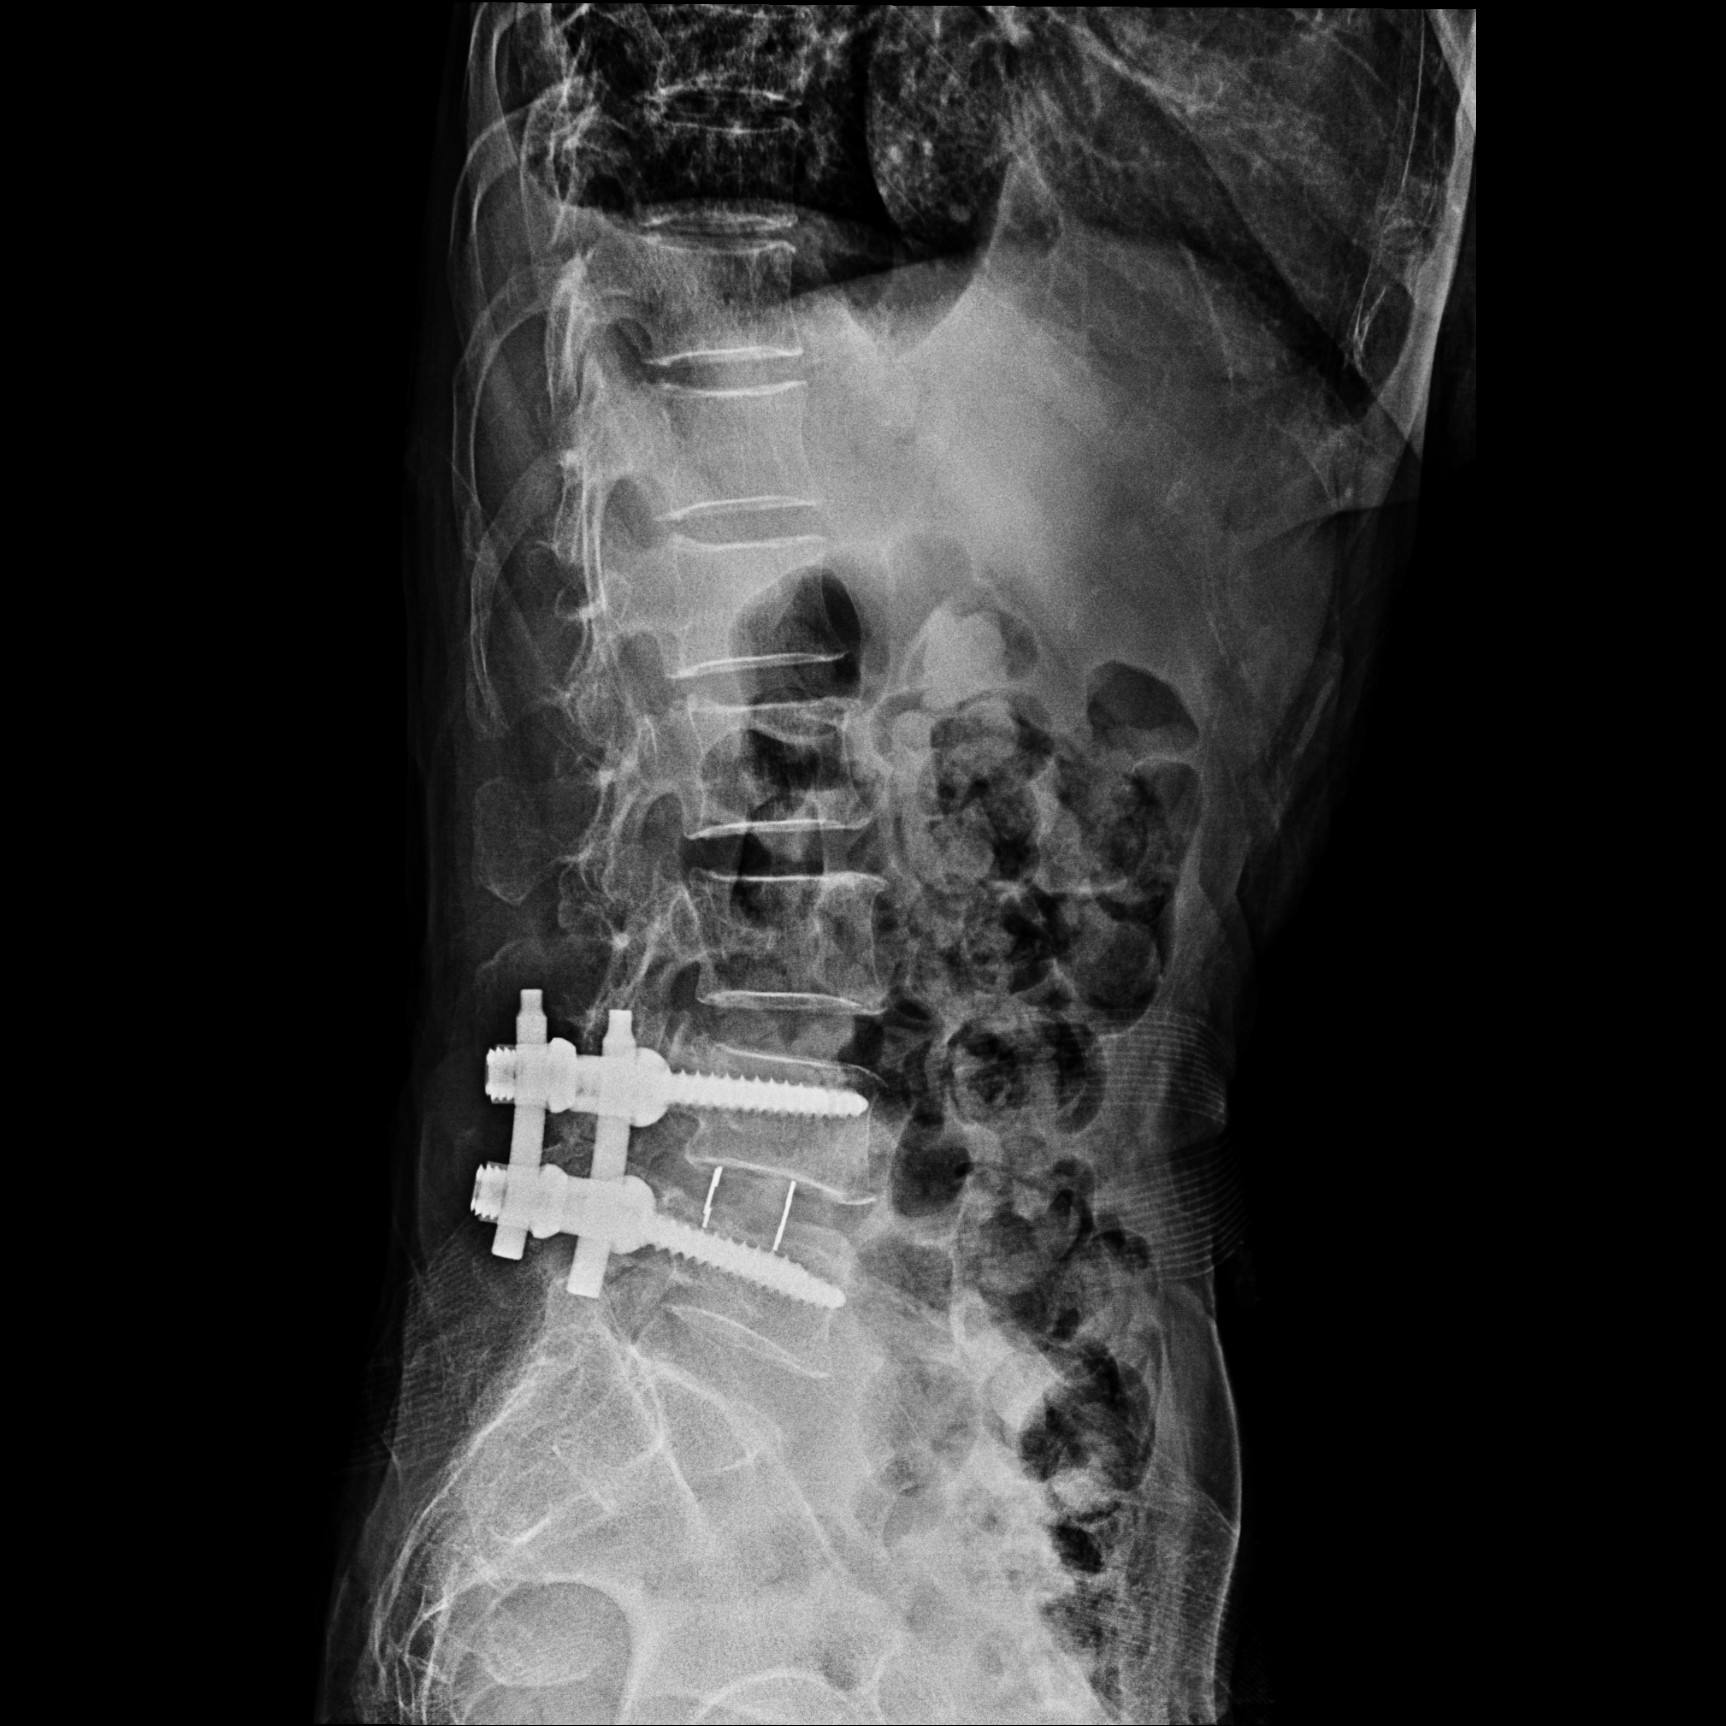

腰椎间盘突出首先考虑保守治疗,保守治疗包括药物、理疗以及腰背部肌肉力量训练等。药物包括非甾体止痛药、肌肉松弛药物以及神经营养药物等。理疗的手段很多,但是谨记避免*力暴**推拿,弊大于利。如果规律保守治疗无效,那就需要考虑手术治疗。手术可以微创椎间孔镜下切除手术或者开大刀的髓核摘除内固定术。

切掉椎间盘,打上钉子,让邻近的椎骨长在一起(图片来源于网络)